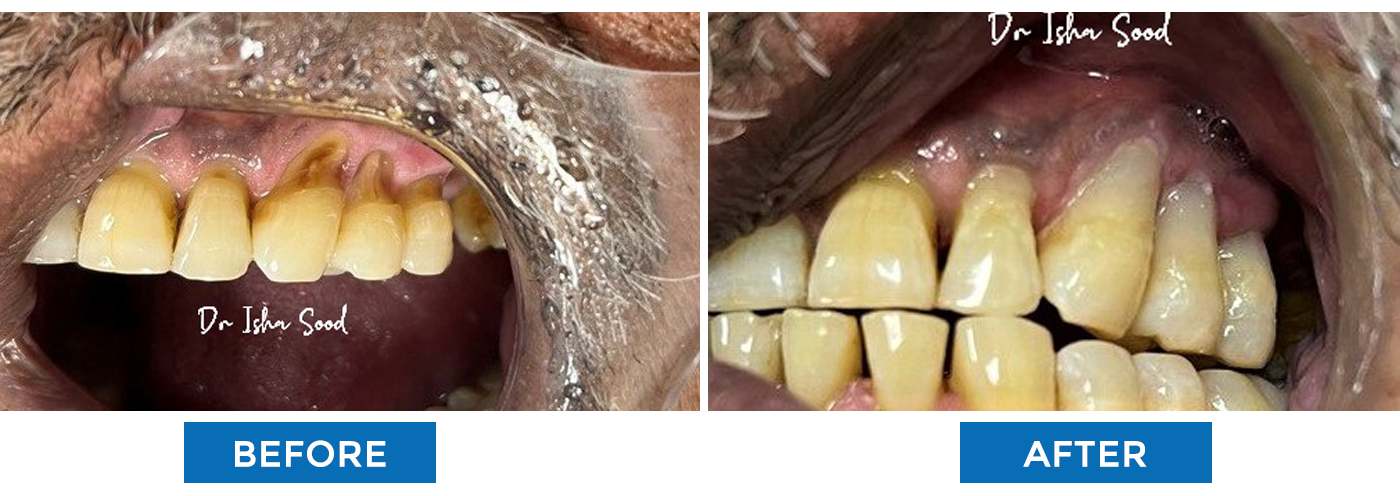

Teeth Cleaning (Scaling)

Gum Surgery To Cover The Root Of The Tooth